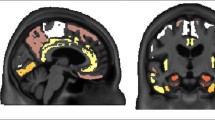

Phosphor-screen autoradiography was performed on brain tissue slides containing the three regions of interest: EC, STS and VC. Strong and selective [F-18]-AV-1451 binding was detected in all tangle-containing regions matching precisely the observed pattern of PHF-tau immunostaining corresponding to the different Braak stages (Fig. 1). Individuals in the low Braak category (stages I–II) (Fig. 1a) showed [F-18]-AV-1451 binding exclusively in EC; intermediate Braak cases (stages III–IV) (Fig. 1b) exhibited tracer binding in EC and STS; and high Braak cases (stages V–VI) (Fig. 1c) showed binding in all three ROIs. Of note, binding was almost completely blocked after incubating the slides with 1 μM unlabeled AV-1451, demonstrating the specificity of the signal. As expected, no signal was detected in the white matter or in non-tangle containing regions in any of the three slides examined. Consistent with our previously reported observations [14], the distribution of the autoradiographic [F-18]-AV-1451 binding closely mirrored the pattern of PHF-1 immunostaining reactivity on adjacent slices with the highest amount of signal being observed in cortical layers III and V, as expected based on the well-known robust density of tangle lesions in those cortical layers, as opposed to the more scattered plaque distribution pattern revealed by Aβ immunostaining (Fig. 1d). Our previous studies using a fine grain nuclear photographic emulsion and immunohistochemistry to obtain resolution at the cellular level, demonstrated that [F-18]-AV-1451 selectively binds to PHF-tau containing lesions, including NFTs (intra and extraneuronal) and PHF-tau containing neurites, but does not bind to Aβ plaques or amyloid-laden vessels [14].

Microphotographs of postmortem brain tissue sections depicting Aβ and PHF-1 tau immunostaining, [F-18]-AV-1451 phosphor-screen autoradiography and blocking conditions in adjacent slides from representative subjects at different Braak stages [2]: a low Braak, b intermediate Braak, and c high Braak, and high magnification microphotographs depicting Aβ and PHF-1 tau immunostaining and [F-18]-AV-1451 phosphor-screen autoradiography of the STS from case #21 (d). [F-18]-AV-1451 binding was detected in all tangle-containing regions matching the pattern of PHF-tau immunostaining across the different Braak stages, but not the Aβ immunosignal. No [F-18]-AV-1451 binding was detected in white matter or in cortical regions lacking NFTs. Scale bar 1 cm (a–c), 2 mm (d). Aβ β-amyloid, IHC immunohistochemistry, NFT neurofibrillary tangles, PHF paired helical filament

Taking advantage of the large collection of well-characterized legacy postmortem tissue samples in our MADRC Neuropathology Core, we selected a series of 22 brains from subjects representing the entire spectrum of Braak staging [2]. We selected blocks containing three brain regions (EC, the cortex lining the STS and the VC) to illustrate the progressive accumulation and predicted spreading of NFTs from transentorhinal/entorhinal cortices to limbic structures and isocortical areas. Our results from phosphor-screen autoradiography confirmed that [F-18]-AV-1451 avidly bound to PHF-tangle containing slices demonstrating very low nonspecific binding to the whiter matter. [F-18]-AV-1451 binding was confined to the EC in cases with low Braak stage (I–II) reflecting the presence of incidental age-related NTFs in these subjects, progressing to the STS in subjects with intermediate Braak stage (III–IV), and extending to the VC in subjects with high Braak stage (V–VI). In agreement with our previous observations [14], the laminar autoradiographic pattern of distribution of [F-18]-AV-1451 revealed a strong labeling in particular of layers III and V, matching the preferential laminar distribution of NFTs on adjacent immunostained sections. These data strongly suggest that [F-18]-AV-1451 is a very promising surrogate marker for estimating in vivo Braak staging; something that may prove to have important practical implications. As it has been recently suggested, knowledge of the in vivo Braak staging using tau PET imaging could be particularly valuable to stratify participants in clinical trials into more homogeneous groups, improving the power of the trial and reducing the required sample size [22]. It could also be useful in helping patients and caregivers understand the likely rate of disease progression over time and develop a plan of care.